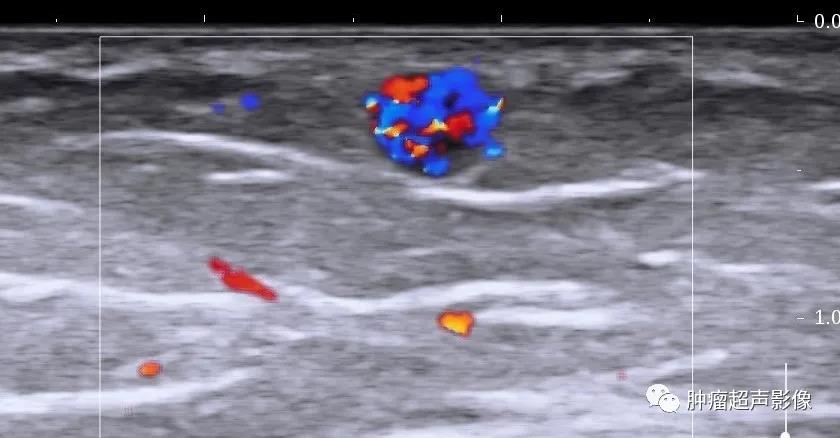

1、血管球瘤:好发于指、趾端皮下或甲床,以剧烈灼痛为主要症状,冷刺激明显,超声表现为边界清的低回声,血流丰富呈“彩球状”、“花篮状”。

病理证实的血管平滑肌瘤,女45,下肢、单发、可移动、疼痛八年的结节,超声表现为皮下边界清的椭圆形低回声肿块,包膜完整,血流丰富,符合典型血管平滑肌瘤。